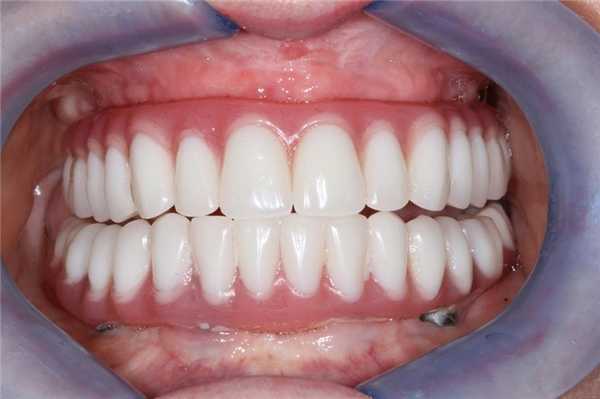

Учитывая тяжелую степень пародонтита, некоторые из его зубов подлежали экстракции, остальные - пародонтологическому лечению, а области дефектов зубного ряда - восстановлению посредством имплантации. Специфика пациента состояла в том, что он много путешествует, следовательно, состояние постоперационной адентии для него является неприемлемым. Кроме того, учитывая аспекты его профессии и высокую социальную активность, съемные протезы также не являлись допустимой альтернативой в данном клиническом случае. После дискуссии относительно всех возможных вариантов реабилитации, пациент остановился на концепции «Все-на-четырёх» с последующей немедленной нагрузкой титановых элементов после удаления проблемных зубов. Вертикальные параметры межчелюстного соотношения не были нарушены, а при улыбке степень обнажения профиля десен в области верхних зубов достигала 3 мм (фото 6). Таким образом, требовалось провести коррекцию позиции мягких и твердых тканей для того, чтобы скрыть линию перехода между протезом и десной. Прикус устанавливали в полурегулируемом артикуляторе. Общее положение зуба сохранялось прежним, дефект во фронтальной области был замещен коронками по размерам несколько шире естественных зубов. Эстетический вид провизорного протеза полностью удовлетворял пациента, а установка новой ортопедической конструкции никак не нарушила прежние окклюзионные соотношения (фото 7 - 9). Хирургический этап проводился в одно посещение с предварительной седацией, и уже через неделю пациент имел возможность вернуться к полноценному образу жизни.

Фото 7. Временный протез: скрытая линия перехода протеза и восстановление эстетики улыбки.

Фото 8. Вид провизорного протеза с ретрактором.